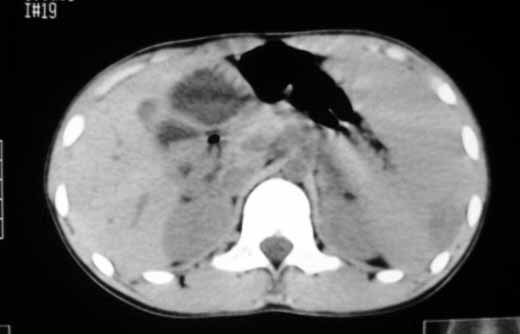

以下是引用zhangzhongshou在2007-5-22 21:04:00的发言:[br]1、脾肿大[br]2、脾脏低密度影,血管瘤?脾梗塞不能除外,建议增强扫描。

以下是引用dyqct在2007-5-22 20:45:00的发言:[br]巨脾,可疑梗塞,建议增强、查血象进一步检查

以下是引用liuyue在2007-5-23 7:57:00的发言:[br]腹主动脉周多个肿大淋巴结,脾大伴三角形低密度影,肠腔积气,考虑:1淋巴瘤2脾大伴梗塞3肠腔积气(肿大淋巴结压迫所致)